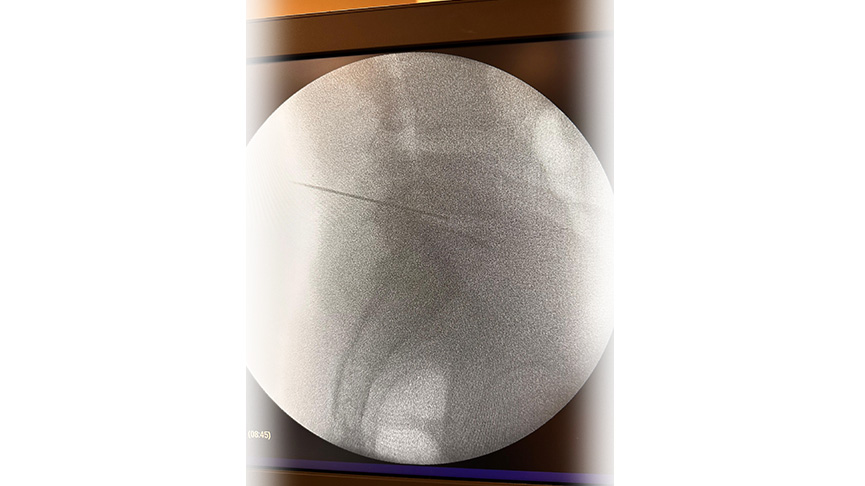

Yöntem: Uygulama lokal ve/veya sedayon anestezi altında yapılır. İşlem öncesinde skopi denilen anlık röntgen çekimi yapan cihaz ile doğru nokta belirlenir

İğne ve Ekipman: Daha sonrasında özel bir iğne veya kateter kullanılarak işlem yapılır. İğne, diskin iç kısmına yerleştirilir ve Plazma RF enerjisi ile işlem yapılır.

Hedef Bölge: Tedavi, fıtıklaşmış diskin belirli bir noktasına yapılır. Bu nokta, ağrıyı başlatan sinirlere baskıyı azaltacak şekilde seçilir.